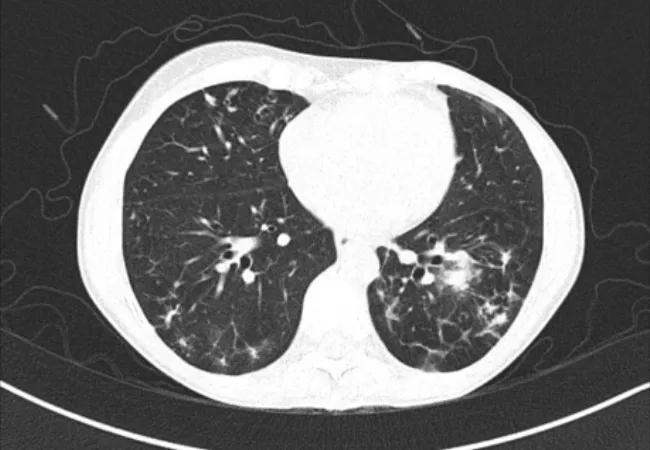

Pulmonary NTM infections due to organisms such as Mycobacterium avium complex (MAC) and Mycobacterium abscessus are being diagnosed with increasing frequency. These organisms are commonly recovered on expectorated sputum cultures or bronchoscopic cultures obtained as part of an evaluation for an abnormal CT chest demonstrating multiple pulmonary nodules or bronchiectasis.

As clinicians, we must raise our awareness of these infections. When a patient presents with fatigue and low appetite, a slow-growing lung infection isn’t usually on the radar. A patient with chronic cough and a clear X-ray oftentimes is suspicious for an indolent lung infection. If the cough does not respond to initial management, a CT chest is often beneficial to exclude NTM pulmonary disease as early nodular bronchiectatic changes often are not seen on standard radiographs.